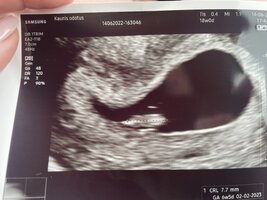

Kiukutellaan yhdessä, sillon mulla sitten jo 8+4. Täällä ultrataan ekalla neuvolakäynnillä.